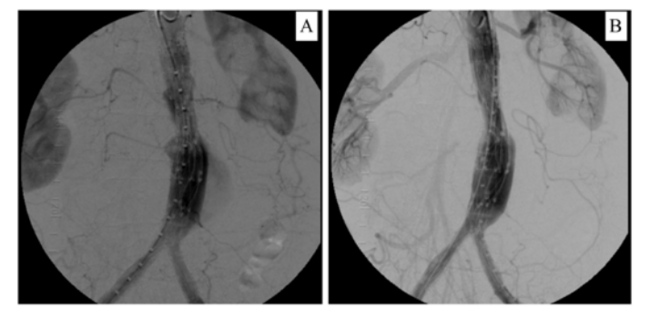

The total incidence of postoperative endoleak was 24.3%, with type II representing 60% of these cases. All other types of endoleak represented an indication for re-intervention (Figure 3, 4). Type II endoleak was an indication for intervention only when sac expansion was detected. We adopted a conservative management approach with a close follow-up strategy with the rest of the cases (Figure 5). This strategy proved safe and effective, with no reported adverse events or ruptures related to this type of endoleak. This is consistent with the Eurostar registry and the report published by Sidloff et al36 after following up on 175 cases of type II endoleak among a cohort of 904 cases of EVAR done in the UK between 1995 and 2013.